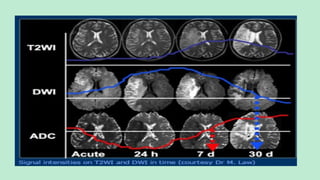

 In humans, diffusion restriction with

reduced ADC has been observed as early

as 30 minutes after the onset of

ischemia.

 The ADC continues to decrease further

and reaches a nadir at approximately 3–5

days.

 Thereafter, the ADC starts to increase

again, and it returns to the baseline value at

approximately 1–4 weeks.

 This is likely due to the development of

vasogenic edema along with the

persistence of cytotoxic edema.

 In a few weeks to months, gliosis develops,

with a resultant increase in the quantity of

extracellular water

 This same pattern of change can be observed in the

diffusion-weighted MR imaging appearance of

ischemic human brain tissue during the evolution of

acute stroke.

 Hyperintense signal is seen with reduced ADC

values from approximately 30 minutes to 5 days after

the onset of symptoms ;

 Mildly hyperintense signal is seen with pseudonormal

ADC values at 1–4 weeks; and variable signal intensity

(because ofT2 characteristics) is seen with increased ADC

values several weeks to months after symptom onset

 The signal intensity in areas affected by acute stroke

on diffusion-weighted images, thus, increases during

the 1st week after symptom onset and decreases

thereafter; however, the signal may remain

hyperintense for a longer period.

 Increased intensity of the diffusion-weighted imaging

signal in the initial few days is due to restricted

diffusion and thereafter is due to an increase of the

T2 signal (T2 shine-through) from the infarcted

tissue.